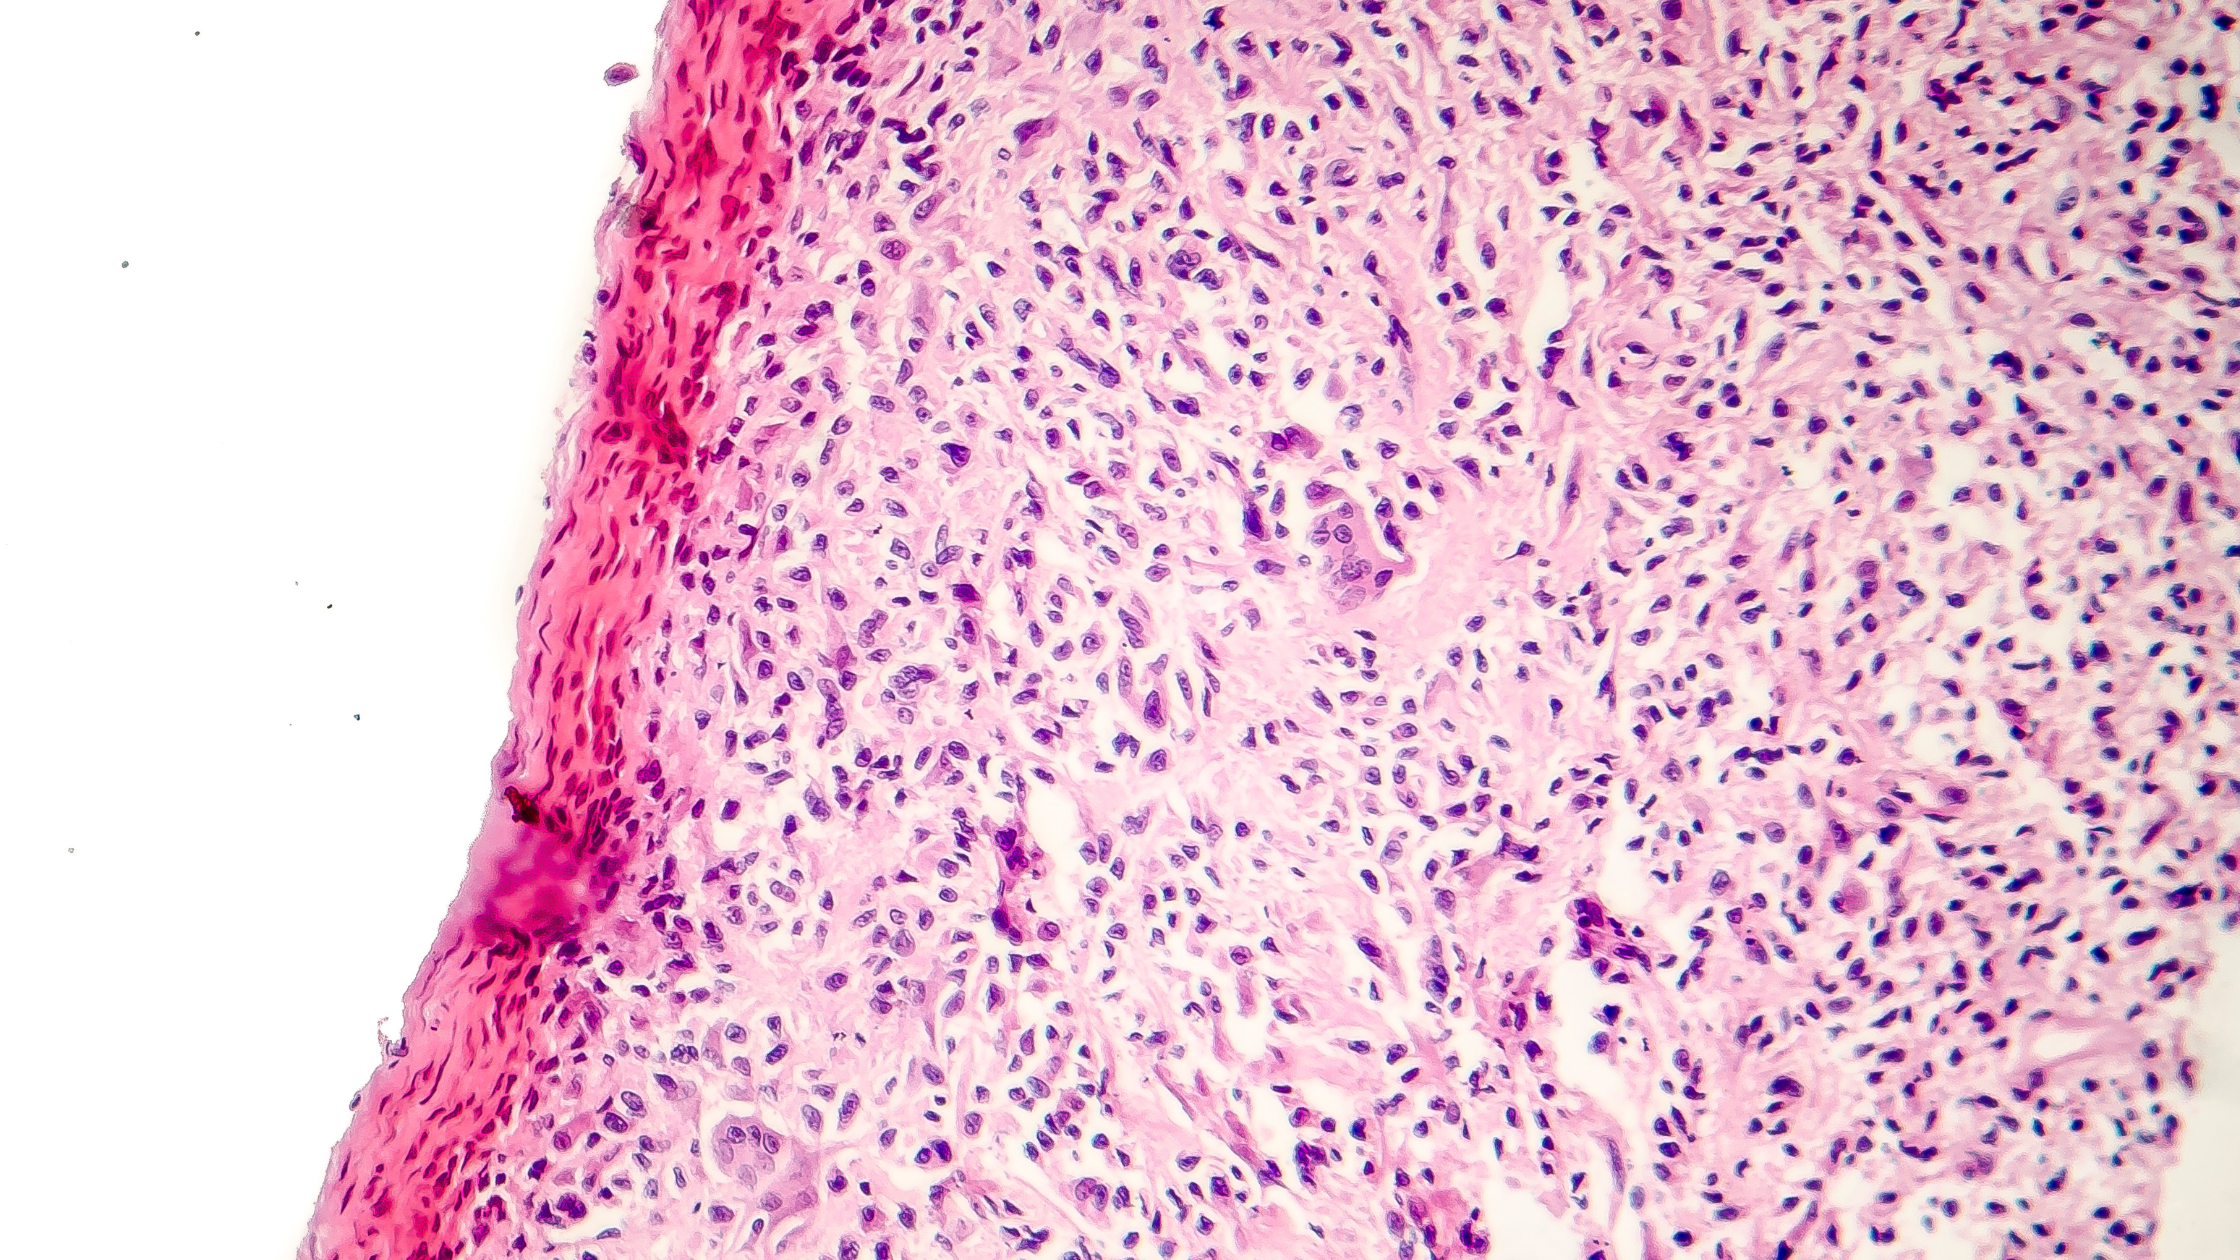

Senescent cells are stressed cells that can no longer divide. When we are younger, our bodies clear these cells through a process called apoptosis, but as we age our bodies aren’t as effective at this.

Although senescent cells no longer divide, they aren’t completely dead. For that reason, they are also called “zombie cells.” They stay in the body and continue to release chemicals. These chemicals can trigger inflammation. When these cells come into contact with healthy cells, they overtake them causing inflammation or even disease to spread.

As we get older, we accumulate more senescent cells. The immune system becomes less efficient and people become more prone to illness and disease. This process also slows down our ability to heal from injury or even learn, since senescent cells do exist in the brain.